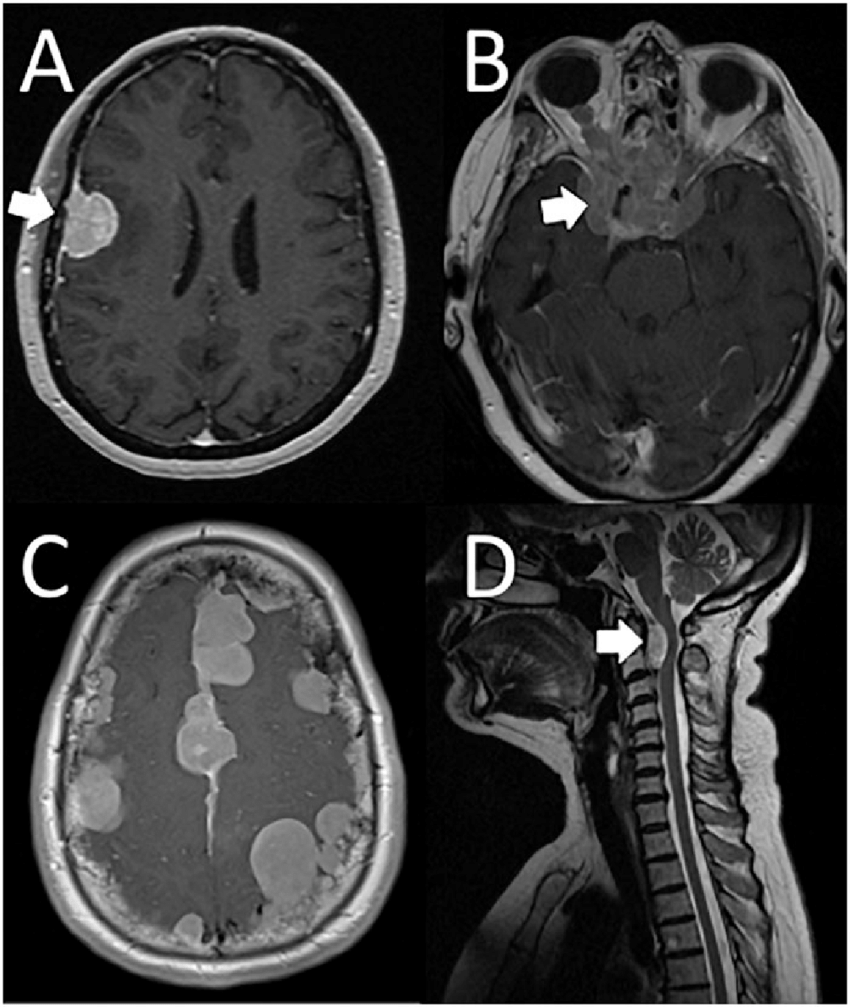

脑膜瘤的症状有哪些表现?脑膜瘤是生长缓慢的轴外肿瘤,约占全部颅内肿瘤的25%。国际卫生组织(世卫组织)根据形态学标准将脑膜瘤分为ⅰ级、ⅱ级或ⅲ级,较高的等级与更具攻击性的...